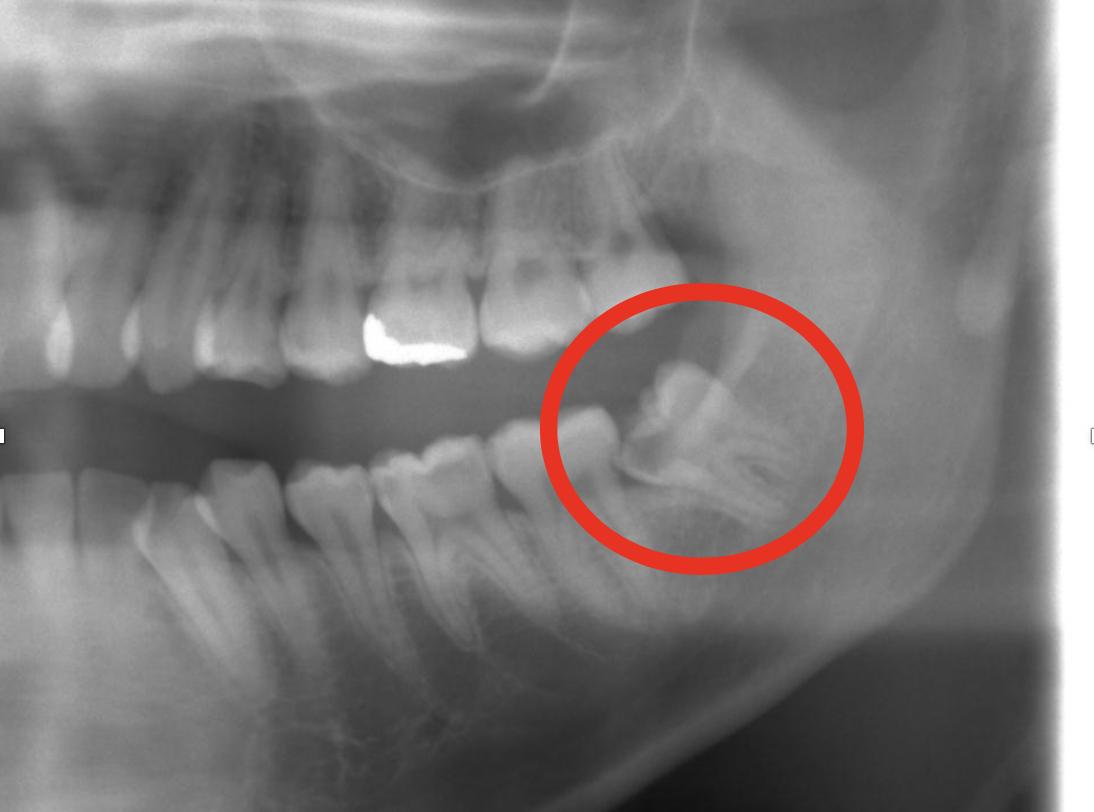

いまはCRがだいぶ発達したと聞く

3826/01/16(金)14:48:40No.1392958205+

銀って俺の歯の銀取って売ったら儲かるみたいな値段まで高騰するかな?

3926/01/16(金)14:48:44No.1392958216+

>いやCADCAMだって保険適用ではあるけど割れやすいし前歯でもなきゃ銀歯が第一候補だよ…

親不知抜くか聞かれるんだけどやったほうがいいのかな

今は大丈夫だけど奥歯の下を圧迫してるそうでそのうち歯列が歪むかもしれない

けど今影響出てないなら無理に抜く必要も無いとも言われている

>親不知抜くか聞かれるんだけどやったほうがいいのかな

>今は大丈夫だけど奥歯の下を圧迫してるそうでそのうち歯列が歪むかもしれない

>けど今影響出てないなら無理に抜く必要も無いとも言われている

さっさとヌいた方がいいよ

圧迫してるなら先延ばしになるだけじゃないかな…

俺が歯並び崩れ始めたのは親不知放置してたからだろうな

元々矯正してたのに

自分のレントゲンじゃないけど親不知が画像みたいな感じで斜めに生えている

他の歯より一段低いから磨きにくいんだよなあ…

>他の歯より一段低いから磨きにくいんだよなあ…

大体の人はまあこうなるから磨きにくいだけなら頑張って磨いていただいて…

どうしても虫歯になるわこれ!ならさっさと抜いてもいいけどそうでないならちょっと削って残すとかもある